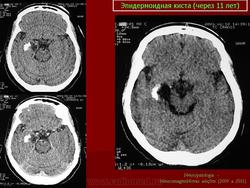

С 1985 по 2000 г.г. в НИИ нейрохирургии им. Н.Н. Бурденко обследовано и оперировано 78 больных с эпидермоидными кистами задней черепной ямки. Изучен клинический симптомокомплекс и КТ, МРТ картина эпидермоидных кист задней черепной ямки.

Качество оперативного лечения оценивалось изучением динамики неврологического статуса, данных КТ, МРТ, как до операции, так и после операции на разных его стадиях. Современные радиологические исследования и микрохирургическая техника полностью обеспечивает радикальное удаление эпидермоидных кист с хорошим после операционным результатом.

Эпидермоидная киста